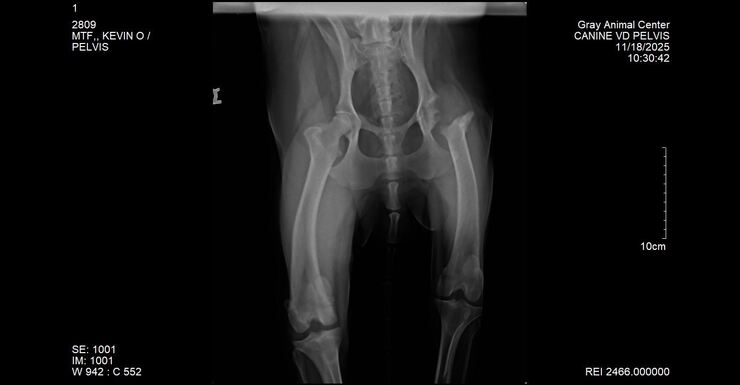

From the moment we walked him, we noticed he had an odd gait—stiff, limping, clearly uncomfortable. We asked for X-rays on the spot, and the shelter staff kindly accommodated. We sent those films to our vet here in Maine as well as had their vet review them. The news broke our hearts.

Kevin needed an FHO (femoral head osteotomy), a surgery where the head and neck of the femur are removed to relieve severe pain caused by a damaged or diseased hip. His injury likely happened long before he entered the shelter system back in January.

This week Kevin saw our vet for further assessment and new X-rays—and the news was devastating.

Kevin now needs a rear cruciate ligament repair and a luxating patella repair.

With Kevin weighing over 110 lbs, he is not a candidate for a simple lateral tie procedure. He will require metal plates, screws, and a very lengthy, restricted recovery. This dog cannot catch a break.